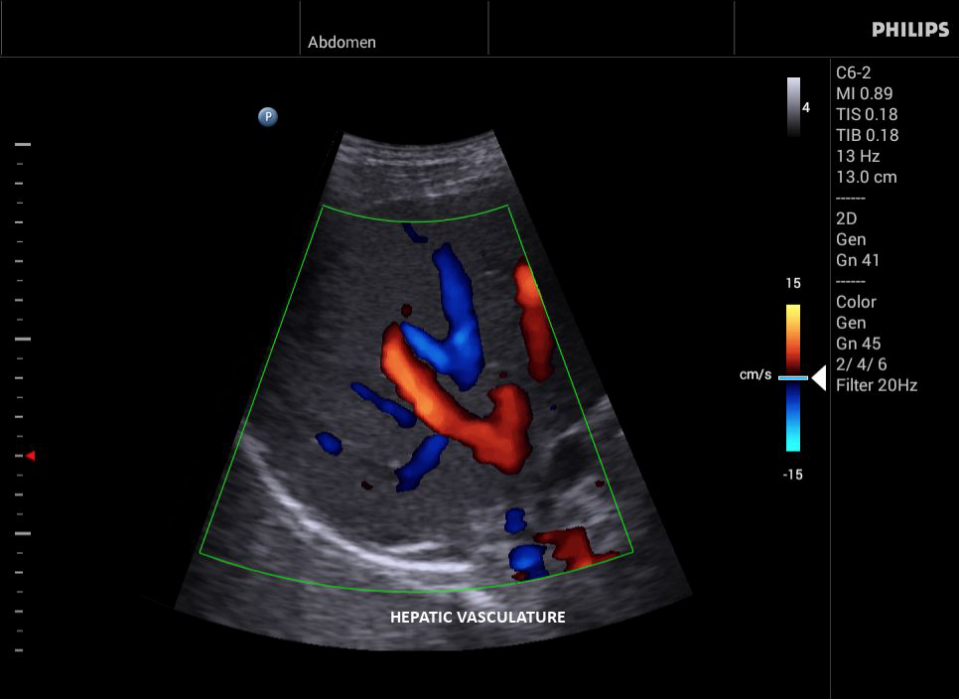

• Конвексный УЗИ датчик Philips С6-2

• Исследования сосудов;

• Цветное допплеровское картирование

• Общие абдоминальные исследования;